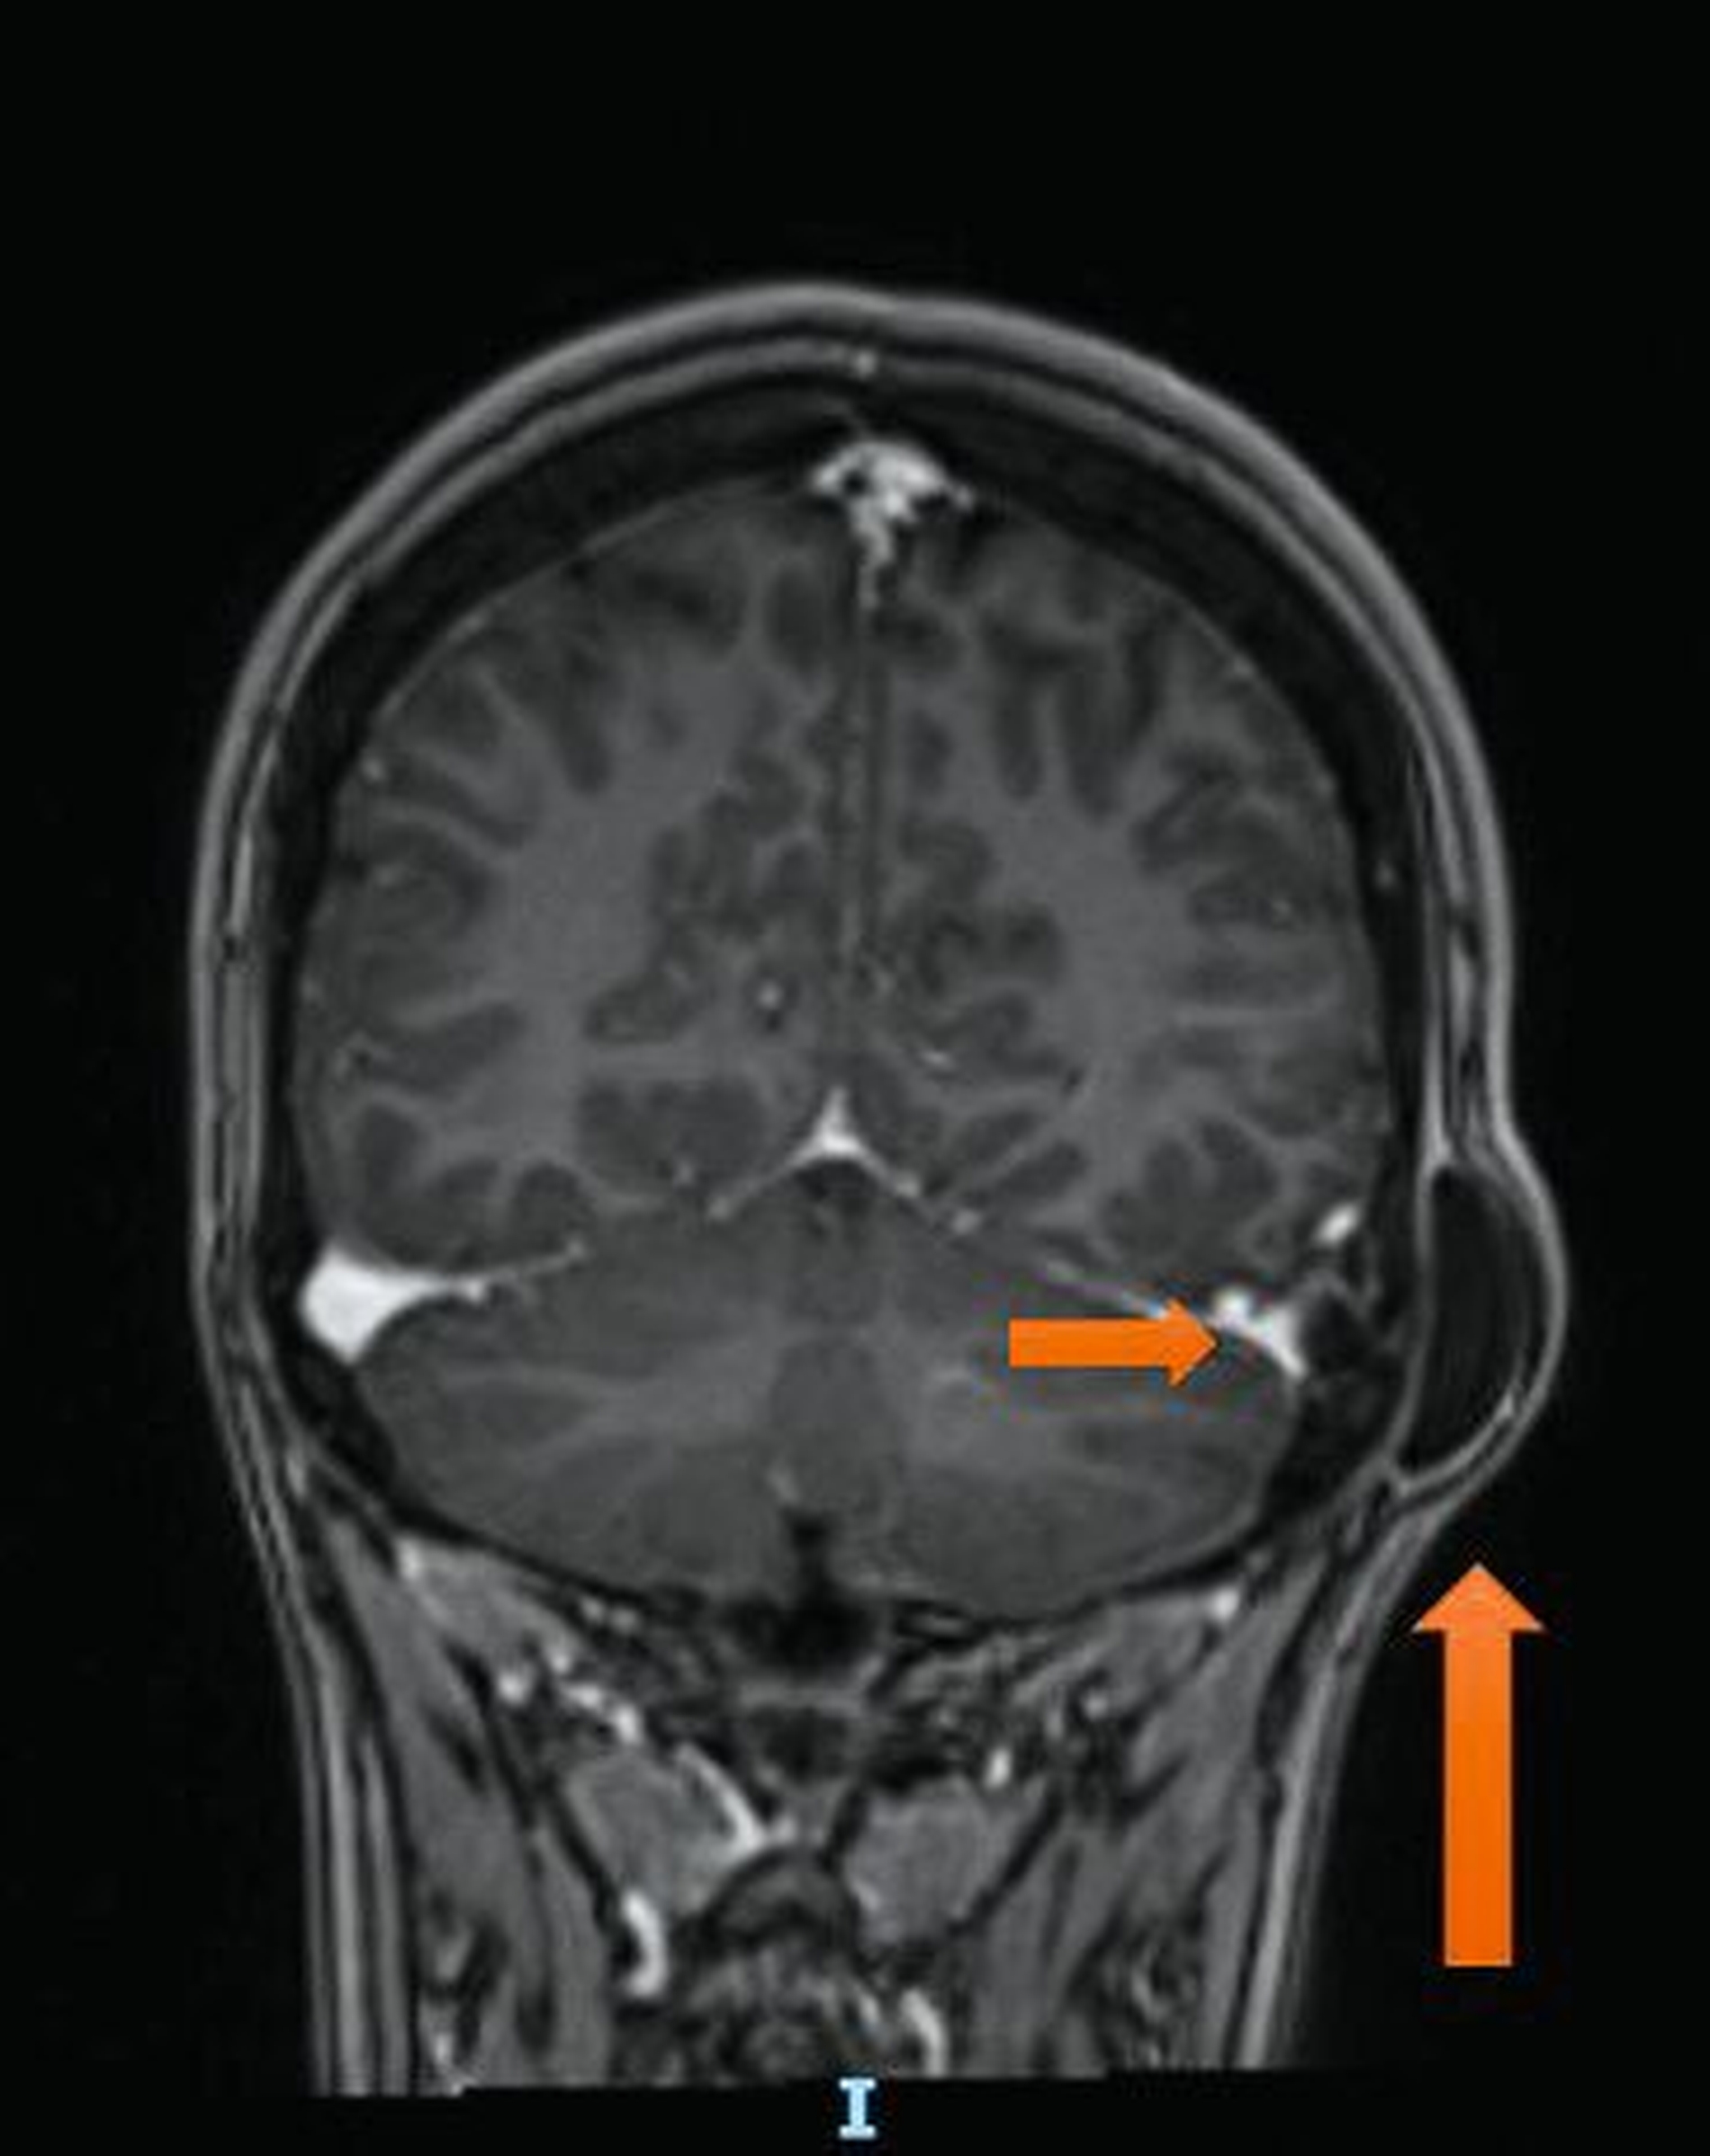

In den vergangenen 18 Monaten war die Raumforderung stark größenprogredient, sodass die Patientin ihren Hausarzt aufsuchte. Dieser veranlasste eine Magnetresonanztomografie, mit der eine 3,5 cm x 1,0 cm x 3,0 cm große subkutane Strukturvermehrung retroaurikulär links mit breitbasigem Kontakt zur Schädelkalotte extrakraniell dargestellt werden konnte (Abbildungen 1 bis 3). Weiter zeigte sich intrakraniell eine noduläre Läsion der Schädelkalotte mit einer Größe von 0,9 cm x 0,8 cm mit einer Impression des linken Sinusknies, die in erster Linie als zystoide Komponente derselben Raumforderung zu werten ist und mit dem extrakraniellen Befund über einen Fistelgang kommuniziert. In der Gesamtbeurteilung wurde der Verdacht einer Epidermoidzyste mit intrakranieller Ausdehnung gestellt. Es folgte die Überweisung an einen niedergelassenen Mund-, Kiefer- und Gesichtschirurgen, der aufgrund der intrakallotären Beteiligung eine Überweisung ins Universitätsklinikum Aachen veranlasste.